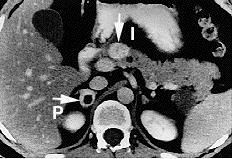

![]() | ![]() |